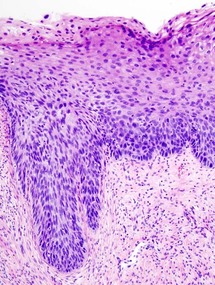

Neoplasia cervical pre-maligna en cuello uterino. Fuente: Wikimedia Commons.